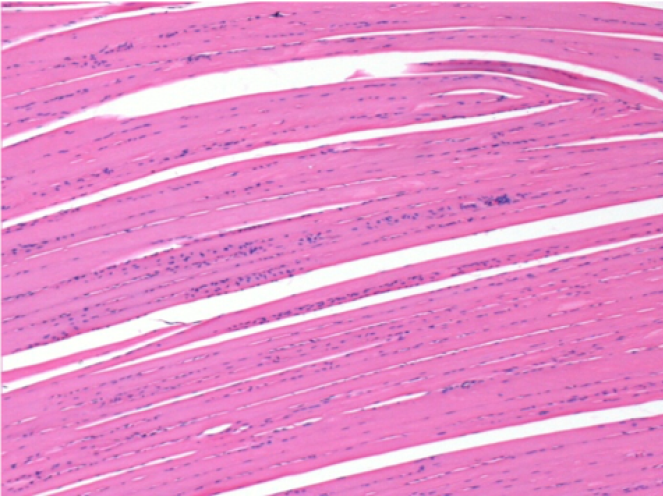

Endopeel Enjeksiyonundan 1 ay sonra sağ pretibial kasta 0.1ml.

Resimlerde siyah olarak görülen şey, bazı bilim adamlarının hayal edebileceği gibi bir nekroz değildir!

Aslında, 4 sonuç dikkate alınmalıdır